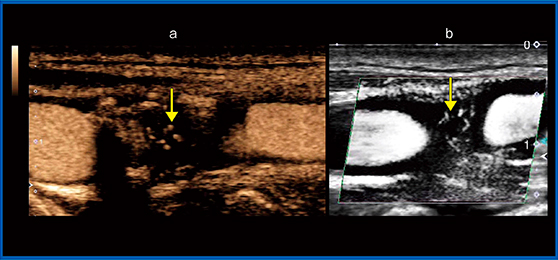

症例1は,72歳,男性,無症候性の頸動脈プラークの症例である。短軸画像の造影超音波(図2a)では,低輝度のプラークの内部に縦に線状に造影剤の流れが描出されている。同じ部分のSMI(図2b)でも血流が確認できた。図3は,症例1の反対側の頸動脈エコーの長軸画像によるプラークの描出だが,こちらも造影剤で描出された血流と同じ部分にSMIでも血流を確認することができた。

図2 症例1:無症候性の頸動脈プラーク(短軸画像)

a:造影超音波画像,b:SMI画像

図3 症例1の反対側血管の頸動脈プラーク(長軸画像)